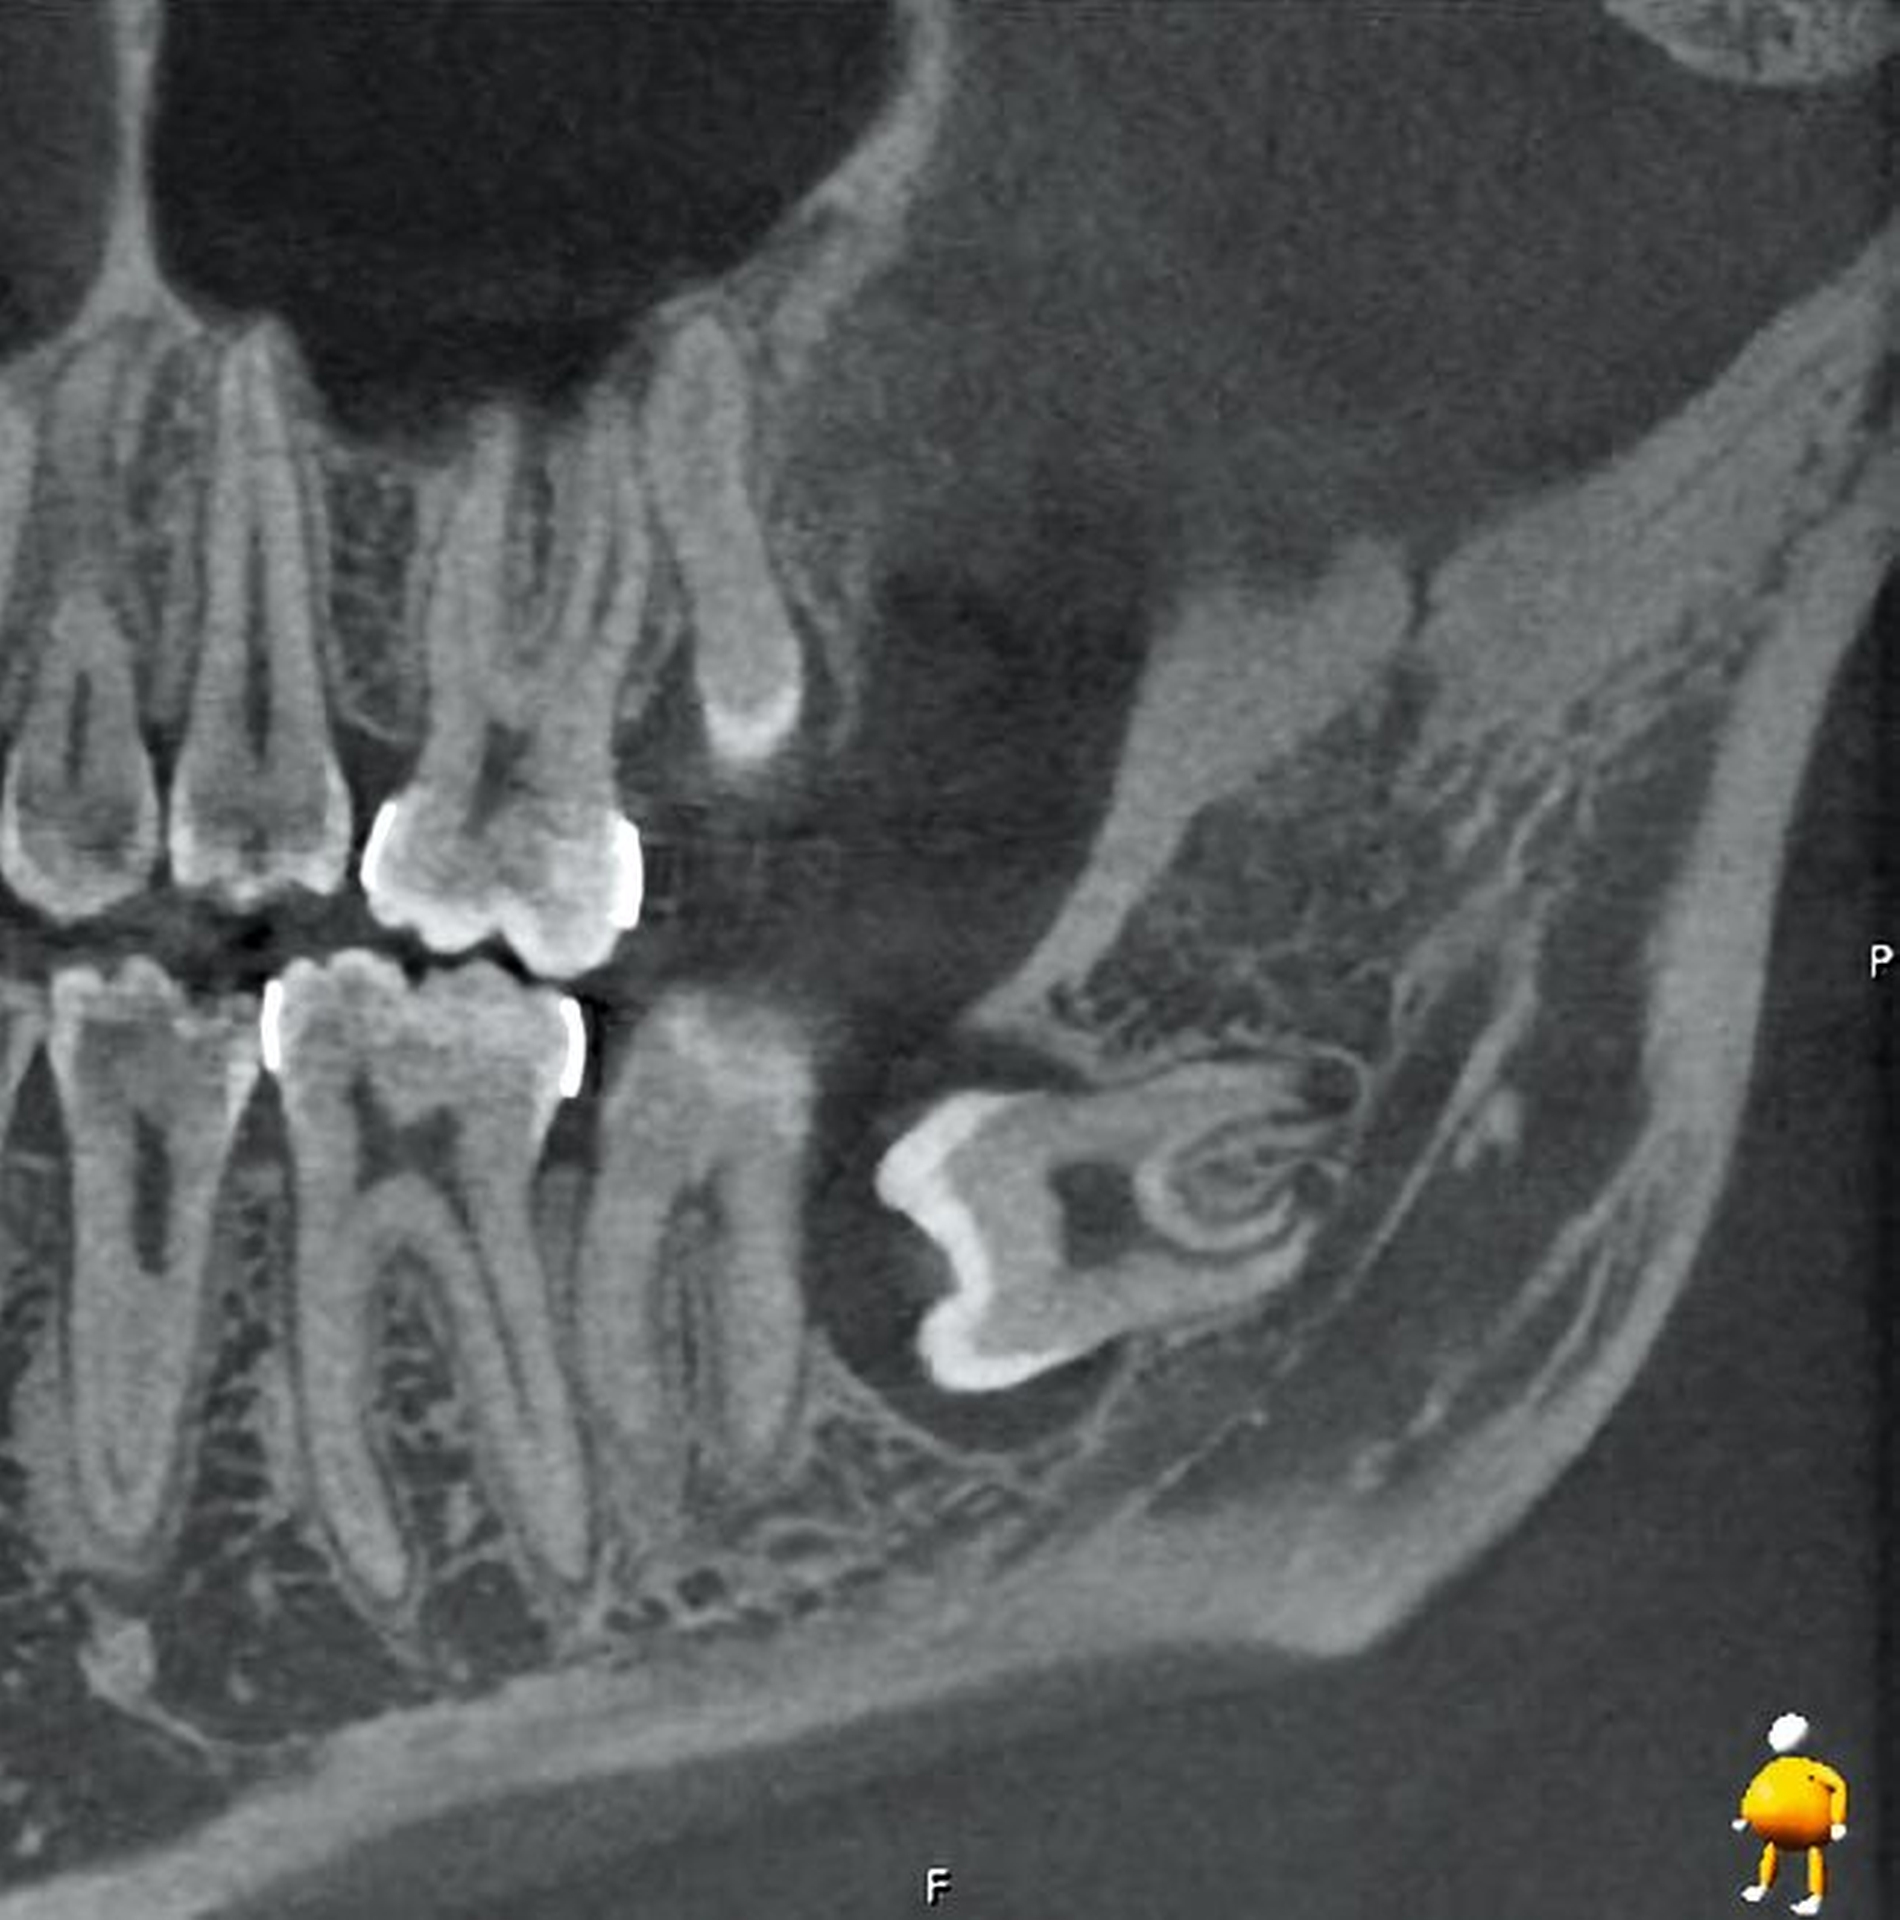

Abbildung 1 zeigt ein Fallbeispiel einer Panoramaschichtaufnahme eines 18-jährigen Patienten mit den genannten röntgenologischen Anzeichen einer engen Lagebeziehung zum Nervkanal, zum einen in Regio 38, aber auch in Regio 48. Zudem befinden sich in Regio 18 und 28 unklare weitere zahnähnliche Strukturen.

Im vorliegenden Fallbeispiel wurde eine dreidimensionale Bildgebung durchgeführt, da sowohl im Ober- als auch im Unterkiefer Risikohinweise bestanden. Zum einen lag eine unmittelbare Lagebeziehung zum N. alveolaris inferior und somit ein erhöhtes Risiko einer Nervschädigung vor, zum anderen bestanden Hinweise auf Lageanomalien und mögliche Doppelanlagen im Oberkiefer, die in der zweidimensionalen Bildgebung kaum beurteilt werden konnten. In der DVT zeigte sich in Regio 48 ein intraradikulärer Verlauf des N. alveolaris inferior durch die Wurzel des nach mesial gekippten und retinierten Zahnes 48 sowie eine perikoronare Aufhellung, die nah an die distale Wurzel des Zahnes 47 reicht (Abbildung 2).